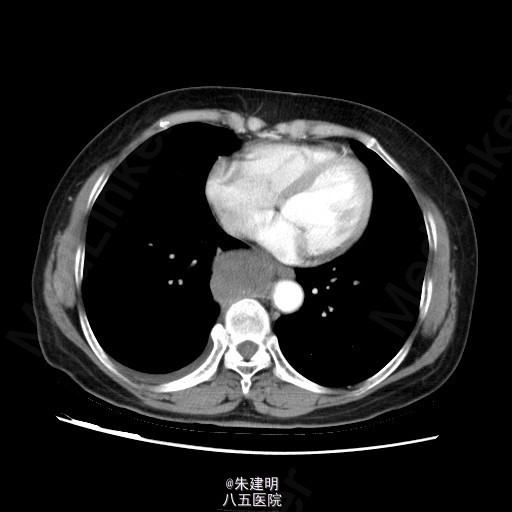

【主诉】 胸部不适1月 【现病史】 患者1月前于当地医院常规体检发现纵隔部占位,为明确诊断,遂来我院门诊就诊。门诊行CT检查(2015-05-07)示:右后下纵膈占位,梭形细胞肿瘤(神经源性等)机会大,右侧少量胸腔积液;左肺炎性小结节机会大,随访。门诊拟诊断为“右侧纵隔占位”收入我科。患者病程中,一般情况可,胃纳二便无殊。

查体: T:36.6℃ P:78次/分 R:20次/分 BP:120/80mmHg 神清,一般可,双侧锁骨上淋巴结未及肿大;胸廓无畸形,呼吸运动平稳,胸廓活动度可;两肺呼吸音清,未及明显干湿罗音。 辅助检查: 门诊行CT检查(2015-05-07)示:右后下纵膈占位,梭形细胞肿瘤(神经源性等)机会大,右侧少量胸腔积液;左肺炎性小结节机会大,随访。

诊断:纵隔肿瘤 处理:患者全麻下行纵隔肿瘤切除术 患者取左侧卧位,常规消毒铺巾,取右后外侧切口经第六肋上缘进胸。探查无胸膜粘连予以分离,无胸腔积液。肿块位于隆突下方,大小约8*7*5cm,质硬,固定推之不动。探查肿块未累及主动脉和两侧主支气管。打开纵膈胸膜,沿脊柱分离肿块,注意保护食管及奇静脉,奇静脉分支结扎后切断。将肿块完整切除。检查无出血漏气,置胸管1根引流,逐层关胸。 术中出血约200ml,未输血,标本送病理。